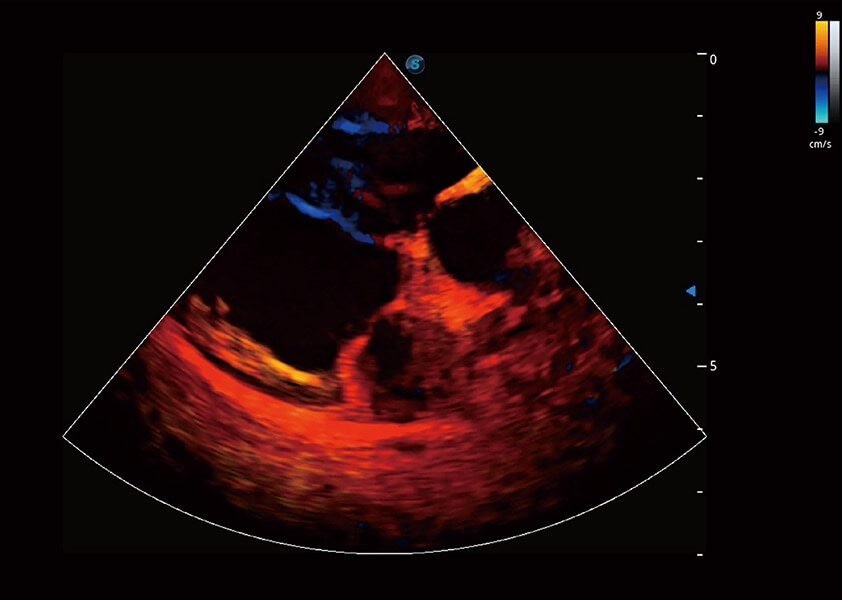

(犬)四腔心血流

(犬)心脏组织多普勒